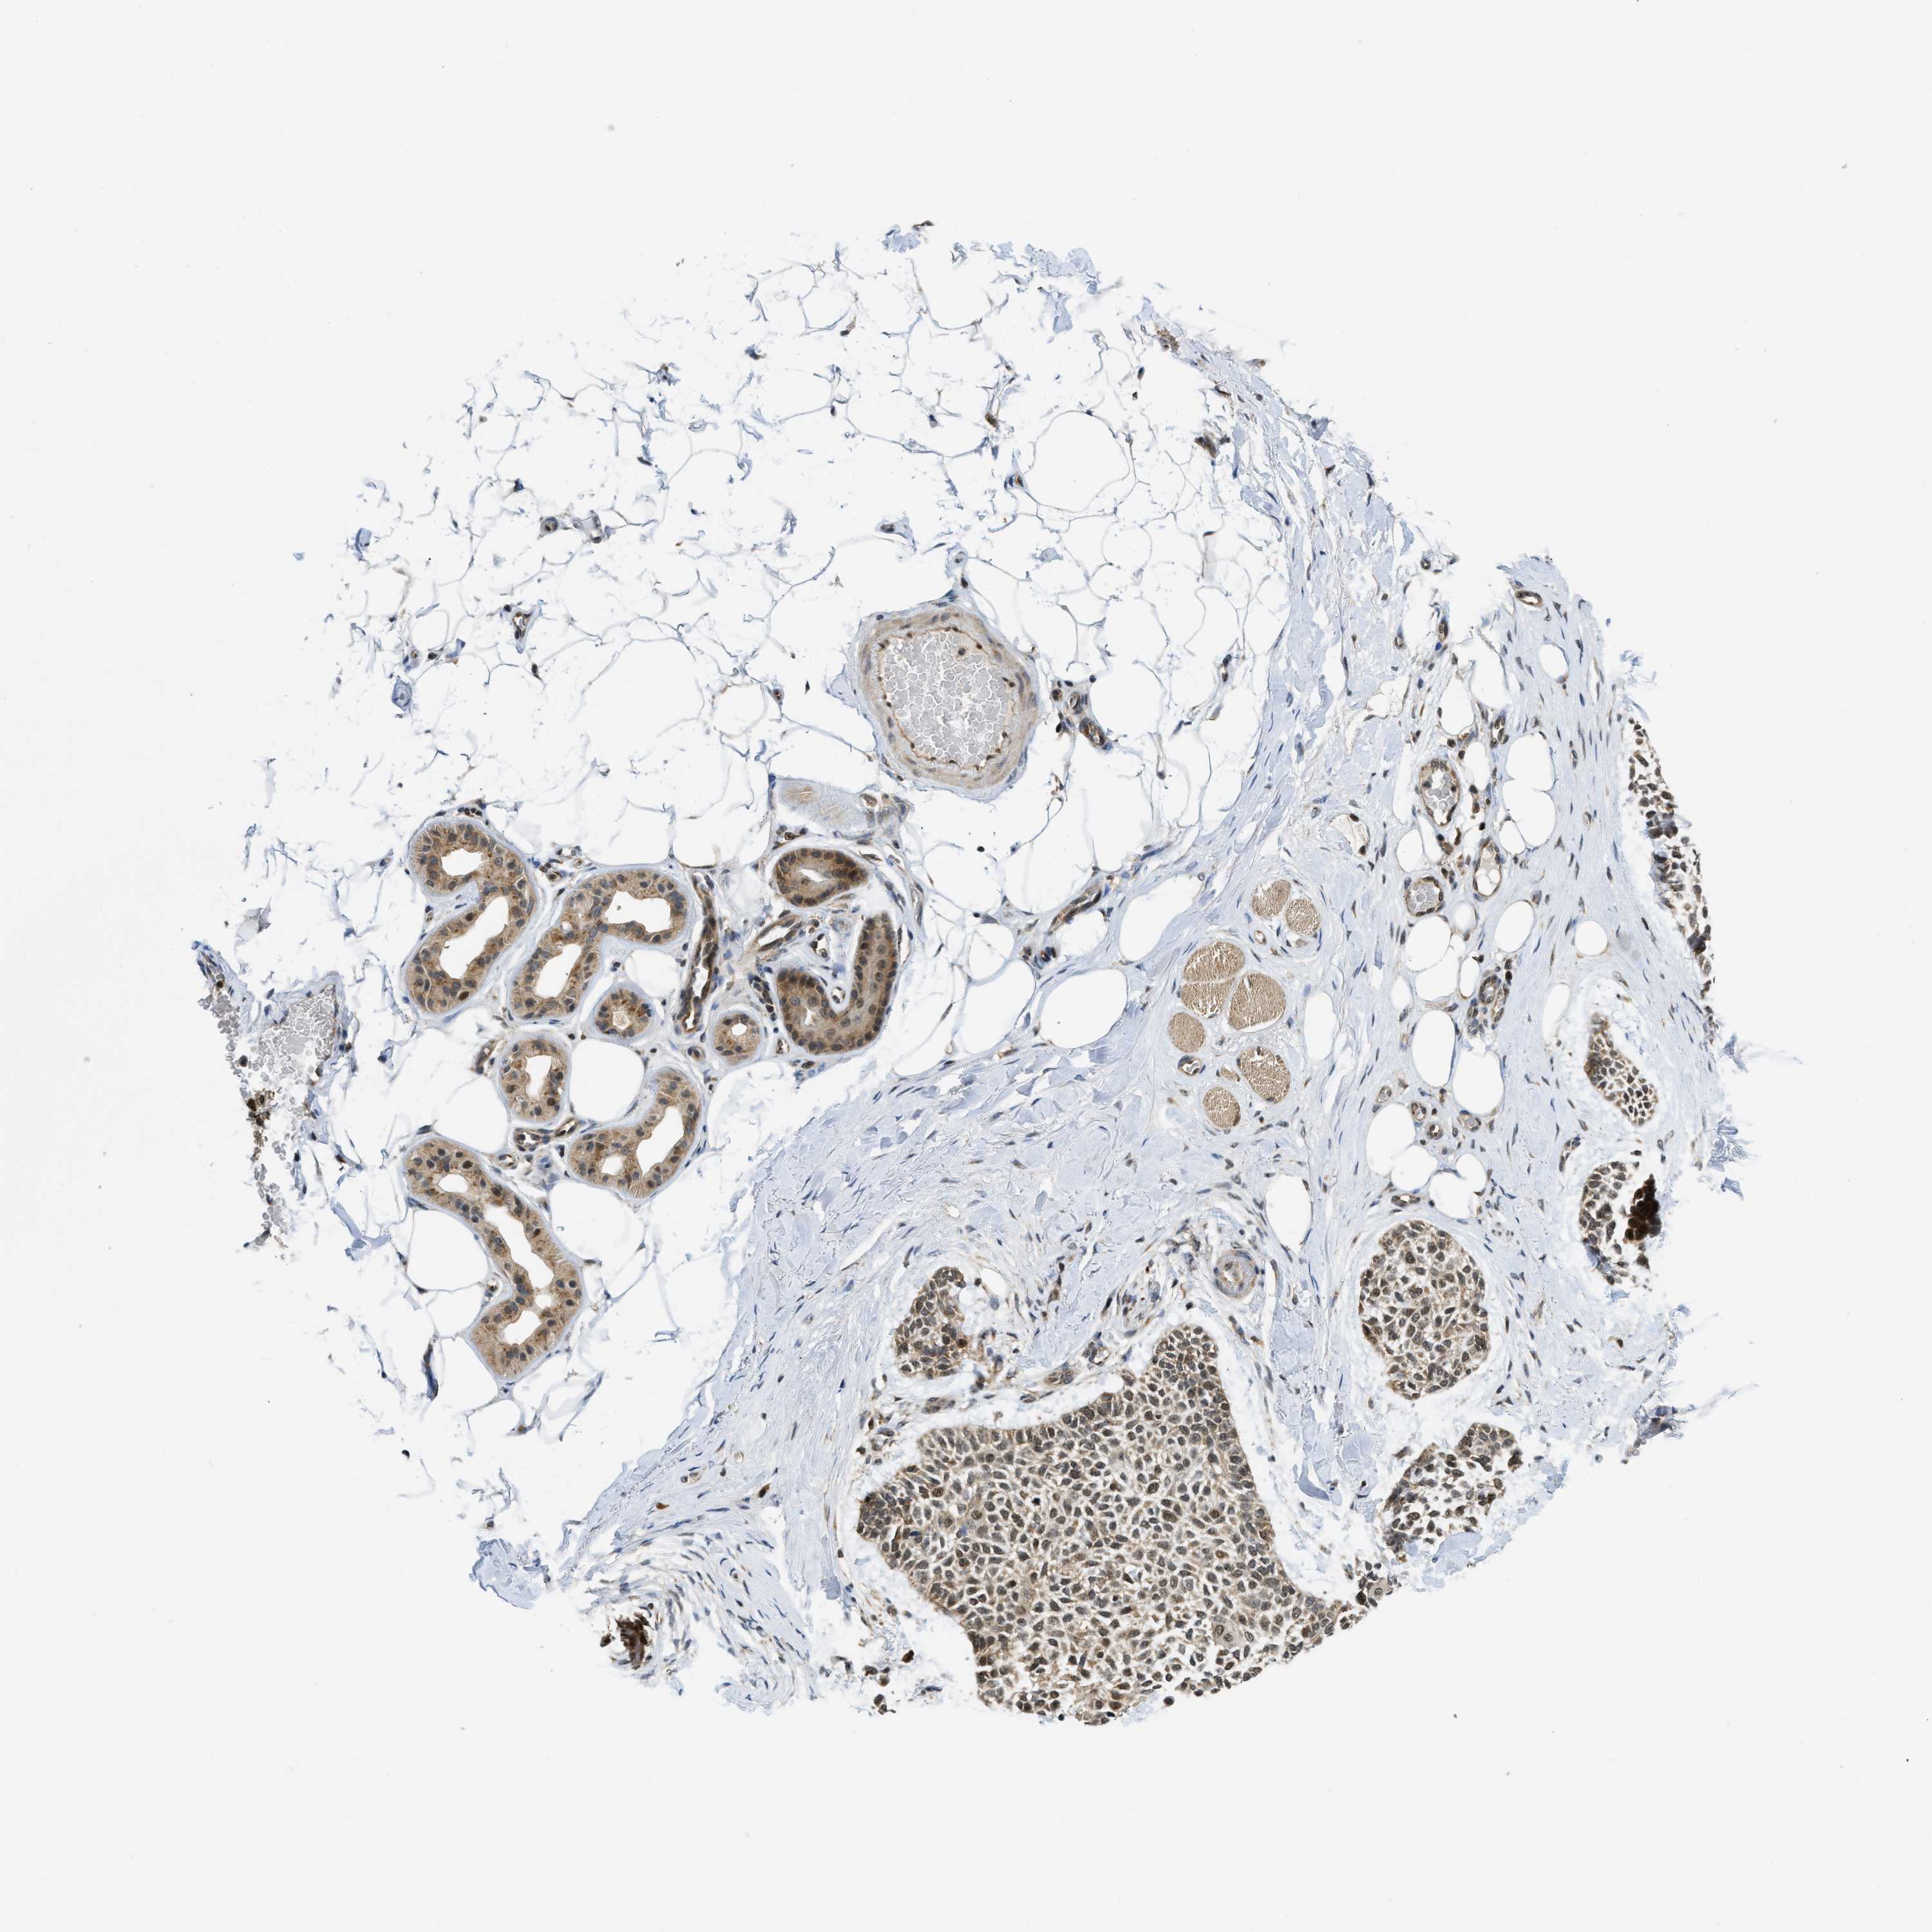

SKIN CANCER - Protein expressioni

A mouse-over function shows sample information and annotation data. Click on an image to view it in a full screen mode. Samples can be filtered based on level of antibody staining by selecting one or several of the following categories: high, medium, low and not detected. The assay and annotation is described here.

Antibody stainingi

Antibody staining in the annotated cell types in the current human tissue is reported as not detected, low, medium, or high, based on conventional immunohistochemistry profiling in selected tissues. This score is based on the combination of the staining intensity and fraction of stained cells.

Each image is clickable and will lead to virtual microscopy that enables deeper exploration of all samples and also displays staining intensity scores, fraction scores and subcellular localization as well as patient and tissue information for each sample.

Antibody HPA024702

Basal cell carcinoma